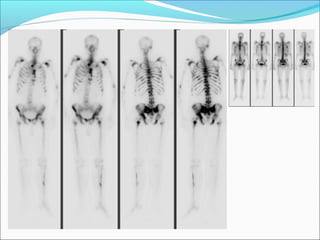

Normal graft

Tc-99m DTPA